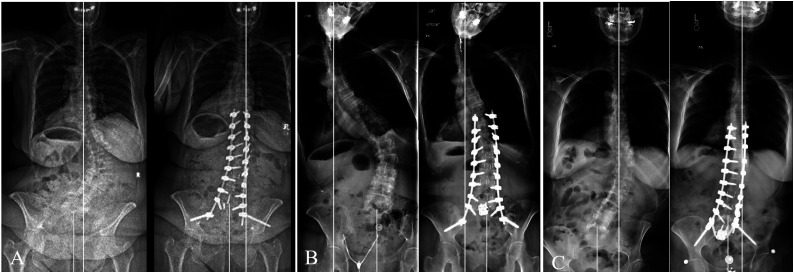

Abstract Image